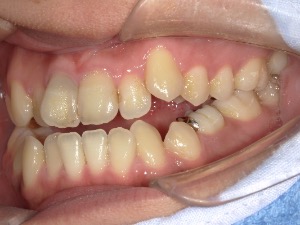

before

患者さんの年齢 30代 男性 症状 ガタガタを治したい 治療内容 ワイヤー矯正治療 費用 88万(税抜) 治療期間・回数 治療期間2年半、通院回数20回 メリット 口元が綺麗 デメリット・リスク 期間がかかることがある 患者さまの声 見た目が良くなった - 矯正治療